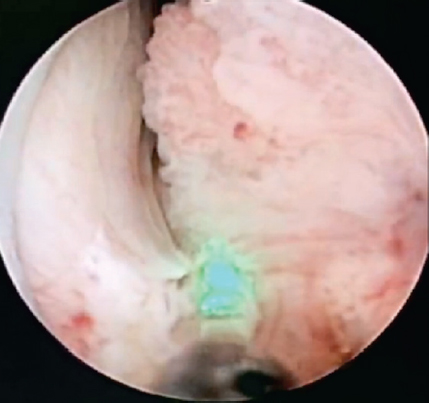

Под эндотрахеальным наркозом после катетеризации ипсилатерального мочеточника в положении пациента на животе под ультразвуковым и рентгенологическим контролем произведена пункция полостной системы правой почки через среднюю группу чашек. Пункционный ход бужирован по гидрофильной струне до 28 Ch и установлен кожух Амплатц. С помощью резектоскопа выполнена ревизия полостной системы правой почки, выявлена мелковорсинчатая опухоль лоханки на ножке (рис. 2). Произведена en-block-резекция стенки лоханки с опухолью при помощи тулиевого волоконного лазера FiberLase U2 (рис. 3).

Рис. 2. Эндоскопическая картина опухоли почечной лоханки. Мочеточниковый катетер в полостной системе правой почки

Fig. 2. Endoscopic picture of a tumor on the renal pelvis. Ureteral catheter in the cavitary system of the right kidney